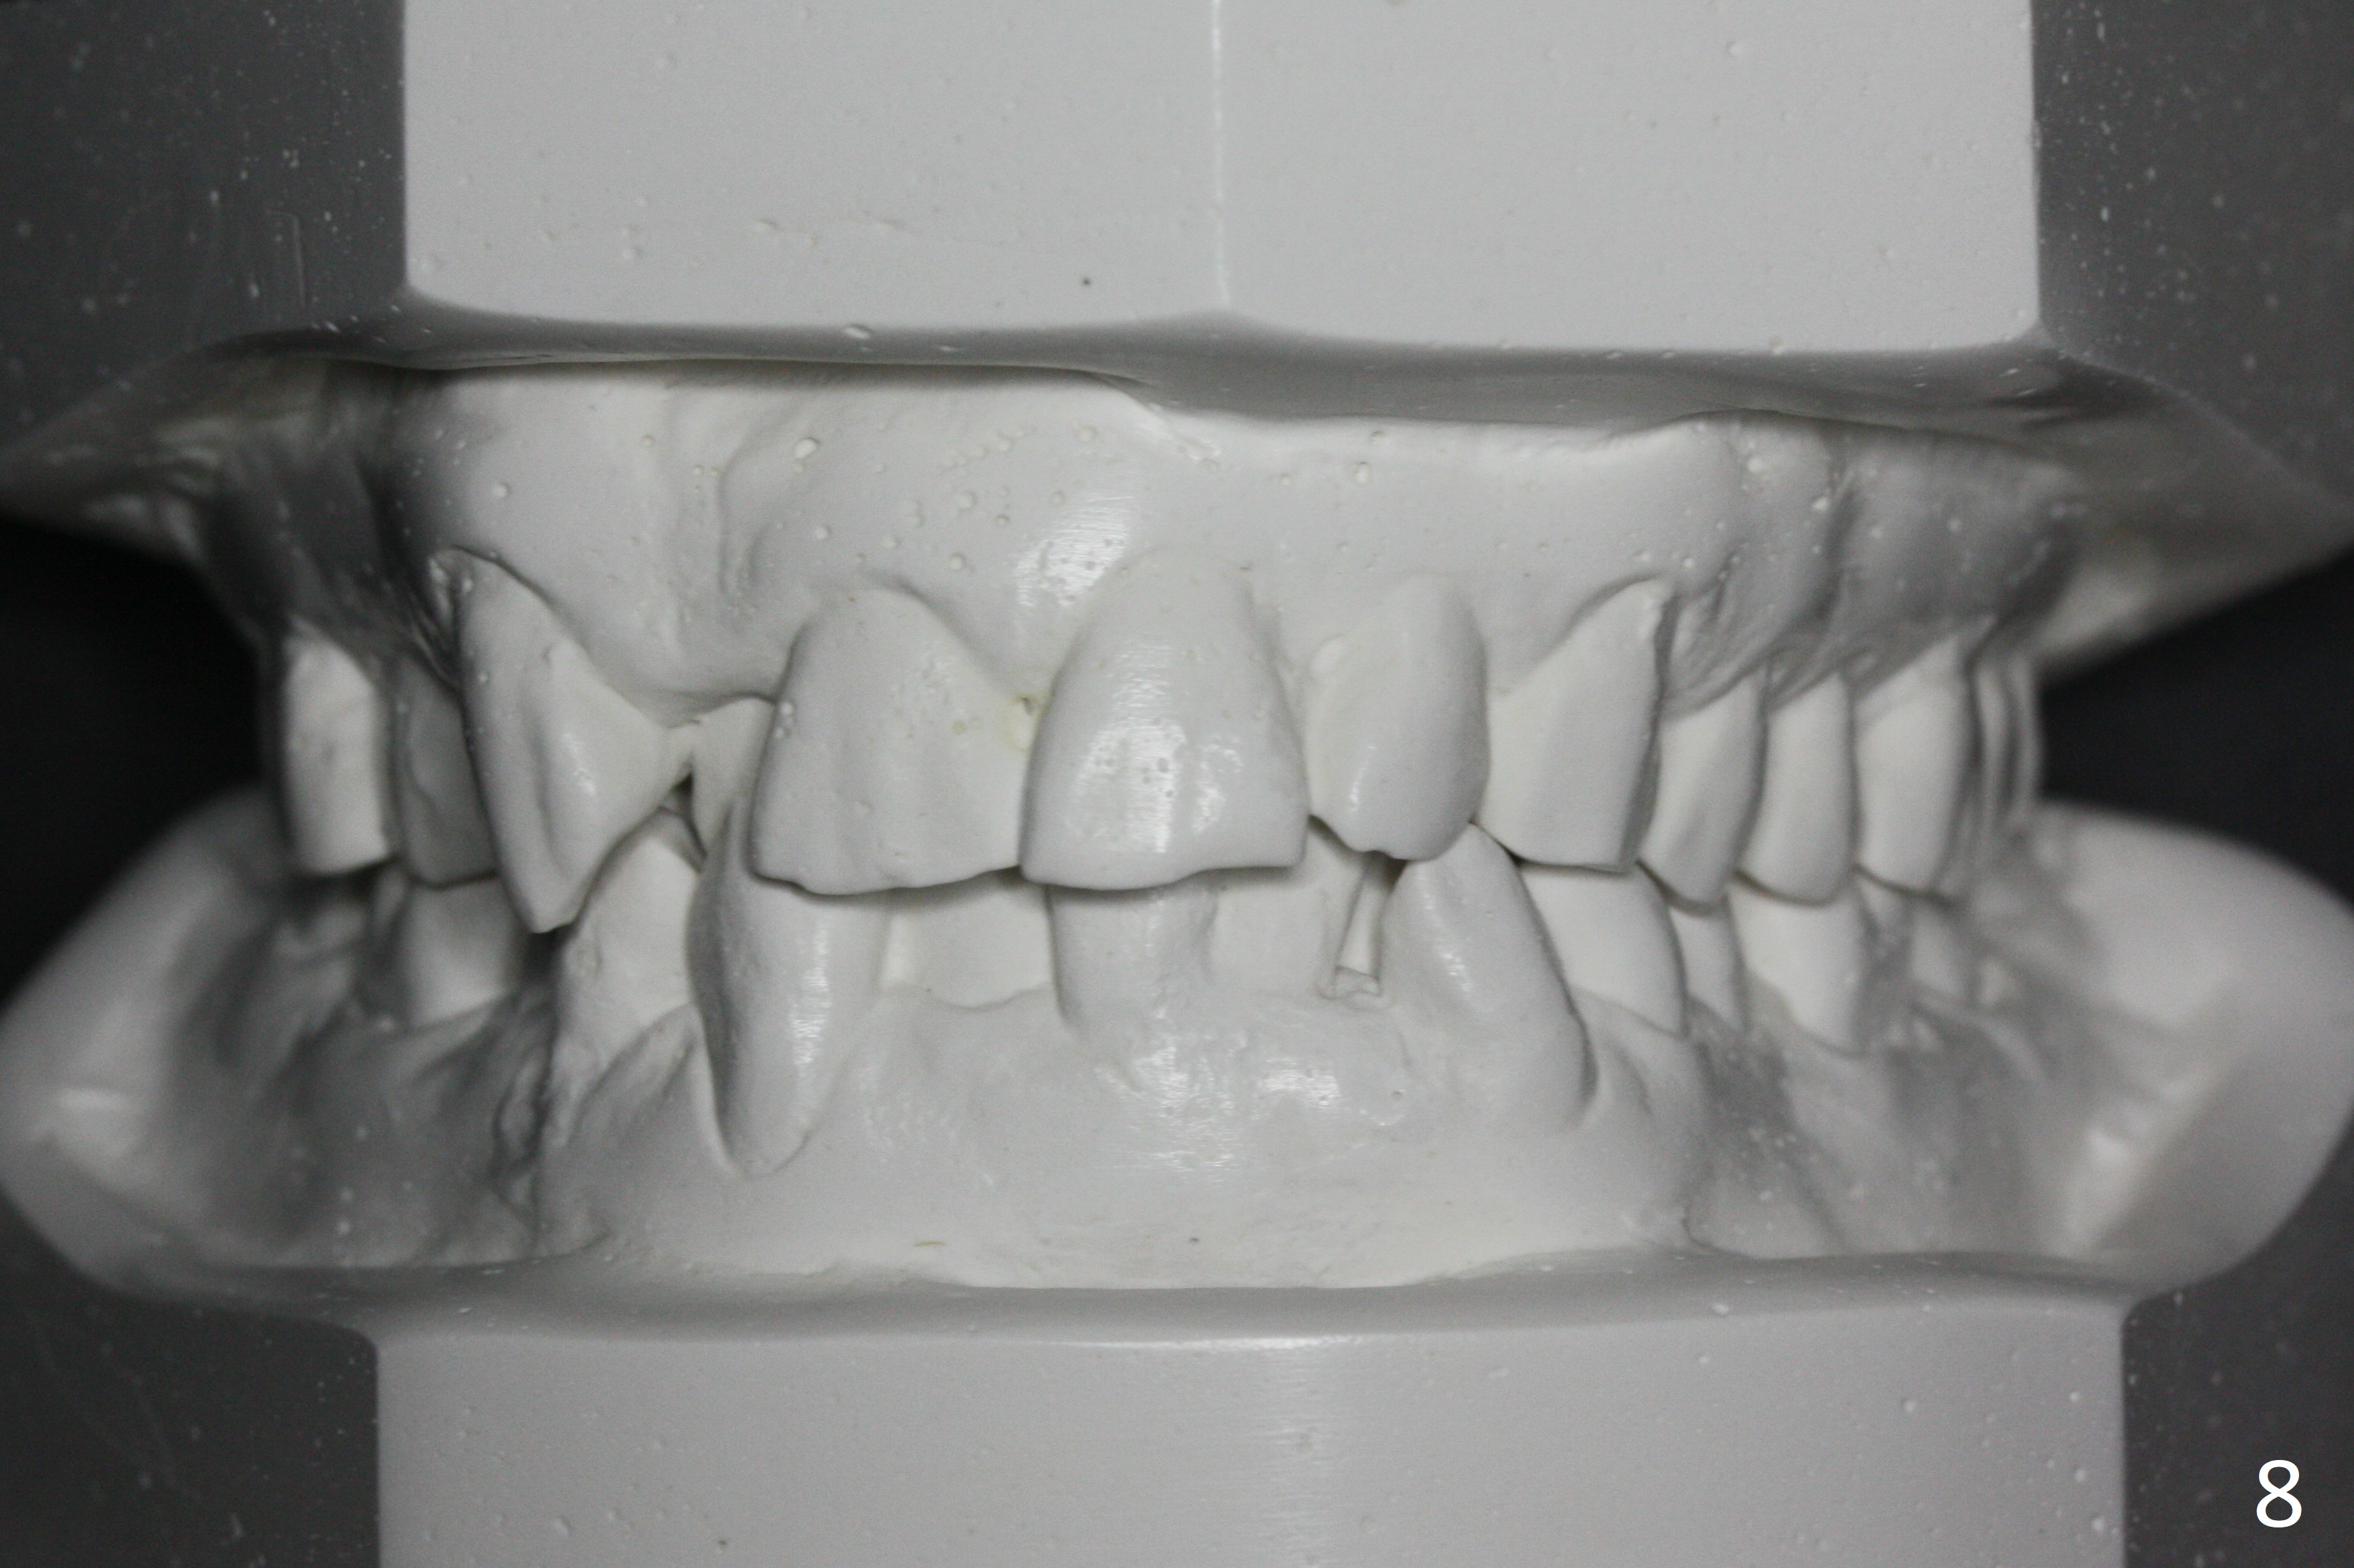

Enough Space For Crowding After Extraction? A 47-year-old man requests orthodontic treatment following SRP in other office (Fig.1-11). For severe crowding and midline shifting, extraction of four of the 1st bicuspids is imminent. Is it enough? To answer the question, model surgery is performed (Fig.12-16). 1st visit: periodontal maintenance, orthodontic consent (emphasizing oral hygiene) extract 4s and possibly L8s and separators. The beauty of this vist is that after local anesthesia and extraction including L8s, it is painless and easy to remove calculus from the proximal surfaces of the neighboring teeth. It is much easier to place separators after extraction. It is expected that there is no gingival erythema when the patient returns for bracketing. Take photos of UR3, similar to Fig.3. Molar banding is also anticipated to be easy with separator placement after extraction. Return to Ortho Cases Xin Wei, DDS, PhD, MS 1st edition 11/23/2017, last revision 04/28/2019